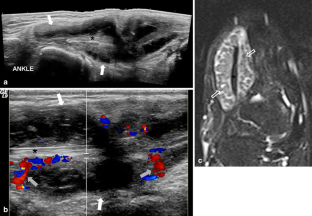

Fig. 1